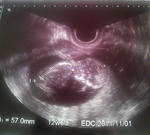

)赤ちゃんの様子です

現在の大きさは5cm

くらいだそうです。だんだんと人の形になっていく様子がわかります